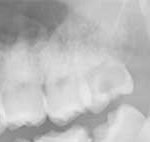

左下 親知らず(淀川区西淡路 27才 女性)

Before

治療内容

親知らずの抜歯